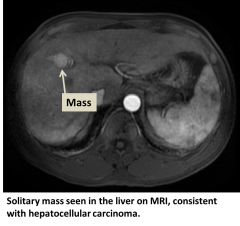

Diagnosis

- MRI